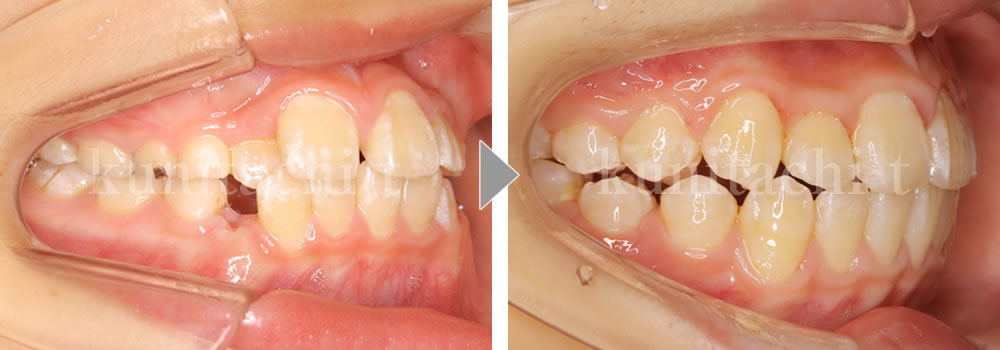

小児矯正治療前後の比較

これから小臼歯が生えそろい、しっかり噛めるようになっていきます。でも、低位舌があると歯並びに影響が出ることも…。「上顎に舌!唇をとじる!鼻呼吸!」良い歯並びをつくるおまじないです。

第2大臼歯も萌出して永久歯列が良い状態で完成しました。